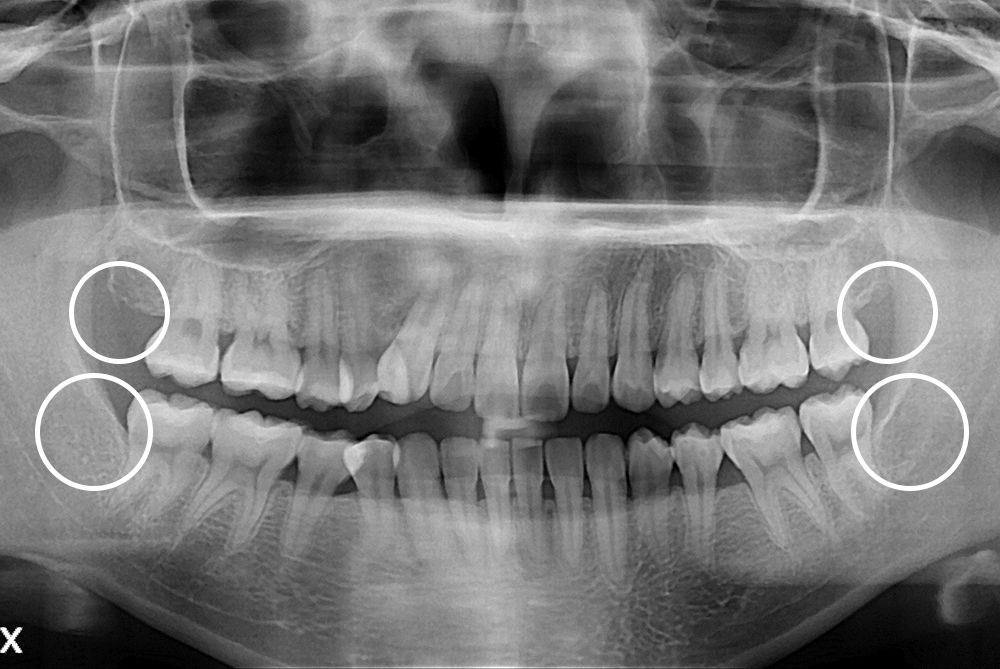

[사랑니] 매복 사랑니 발치

치료전 : 2017-12-19

세종치과는 구강악안면외과학 박사이신 원장님이 발치하는 치과입니다.